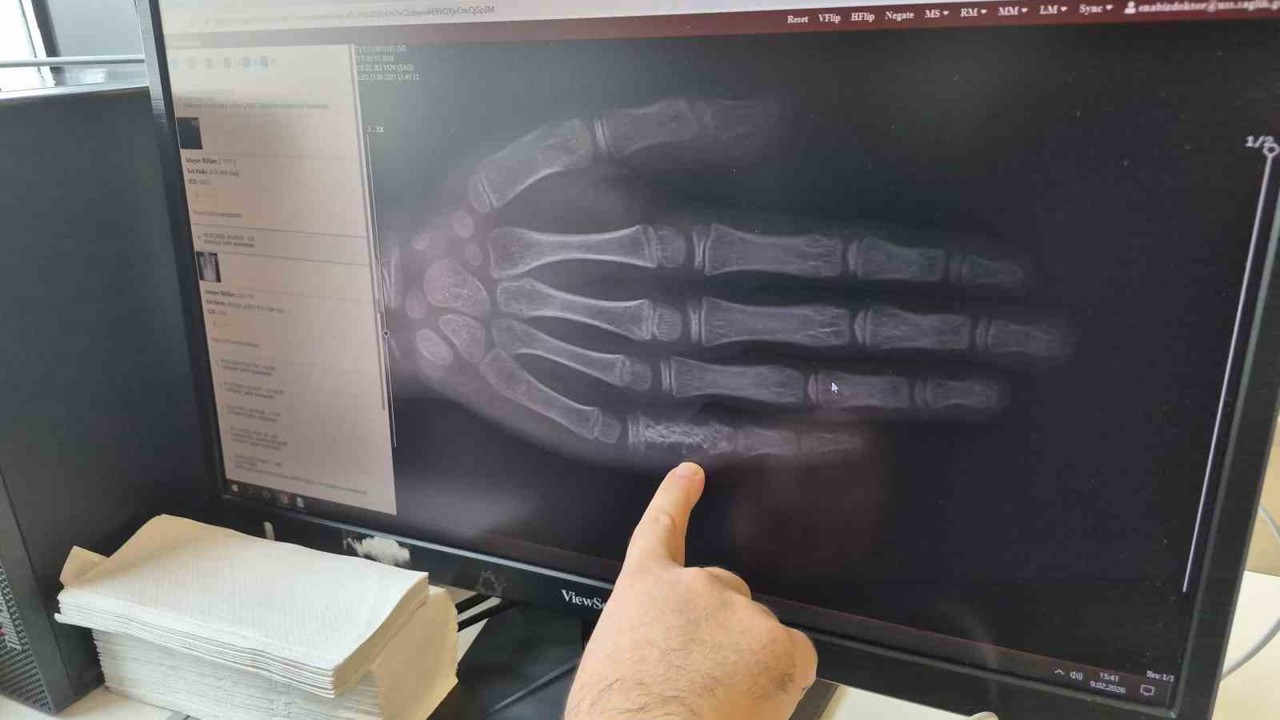

Doç. Dr. Ersin Töret, 15 Şubat Çocukluk Çağı Kanser Günü kapsamında bilgilendirmede bulundu. İstatistiklere göre her 100 hastadan birinin kanser olduğunu söyleyen Dr. Töret, bu vakalar arasında çocukluk çağı kanserinin de görüldüğünü ifade etti. Eskişehir’de her ay 5 ila 7 arasında çocuğun kanser tanısı aldığını belirten Töret; bu vakaların büyük bölümünü lösemi olarak bilinen kan kanserinin oluşturduğunu, ikinci sırada beyin tümörleri ve üçüncü sırada ise lenf bezi kanserlerinin yer aldığını dile getirdi.

Konuyla ilgili açıklamada bulunan Çocuk Hematoloji ve Onkoloji Doç. Dr. Ersin Töret, "Bu kanserlerde genelde ailelerimiz açısından farkındalık oluşturmak önemli. Erken tanı hastalığın tedavi sürecinin daha kısa sürede tamamlanmasını sağlarken, yaşamda kalma şansını daha da artırmaktadır. Hastalarımızda özellikle 3 günden daha süren uzun ateş olması, kemik eklem ağrıları olması, ailenin çocuklarına banyo yaptırırken veya kıyafetlerini değiştirirken ellerine sert kitleler gelmesi dikkat edilmesi gereken belirtilerdir. Ayrıca keyifsizlikleri, oyun oynamaya karşı isteksizlikleri varsa, çocuk rutin olarak ilgilendiği uğraşlarını yapamıyorsa doktor tarafından değerlendirilmesinde fayda var" şeklinde konuştu.

Eskişehir Şehir Hastanesi’nde hem hastalığın tanısı için gerekli tetkiklerin hem cerrahi işlemlerin yapıldığını vurgulayan Dr. Töret, "Pek çok kanseri burada hastanemiz çatısı altında tedavi edebilmekteyiz. Çocukluk çağı kanseri de buna dahil. Çocukluk çağı kanserleri genellikle biraz kötü piyango gibidir. Özellikle ilk 5 yaşta görülüyor. Kökeni erken dönem hücresel gelişime dayanan bazı lösemi türleri ilk 5 yaşta daha sık görülmektedir" ifadelerini kullandı.